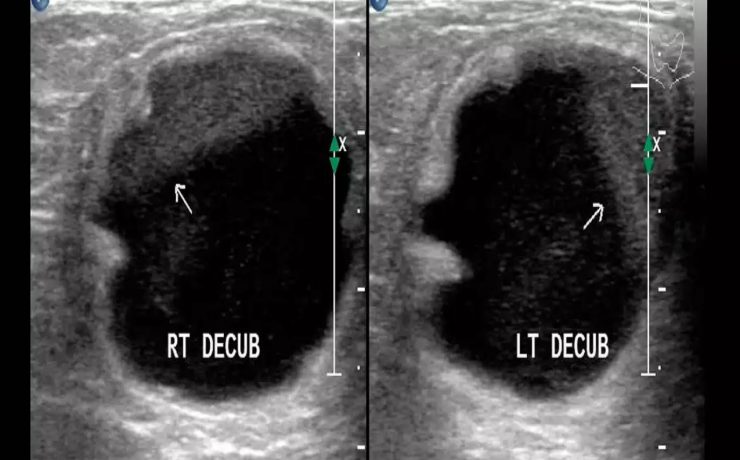

En este estudio se analiza la utilidad del ultrasonido en el estudio de la paciente estéril, específicamente con ultrasonido con aplicación de doppler, de Power doppler y la ecografía 3D para analizar los cambios cualitativos y cuantitativos que se observan en la irrigación del ovario en pacientes estériles, en pacientes